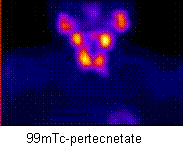

with a parathyroid adenoma (arrow). In the 99mTc pertecnetate image it is seen a

homogenuos uptake in the thyroid gland.